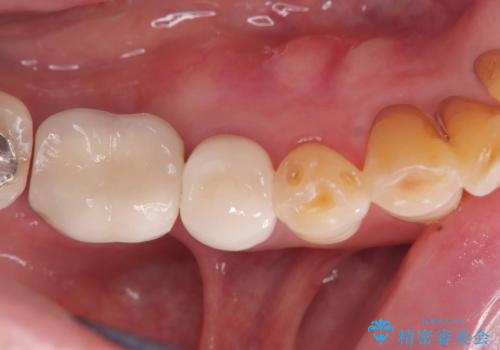

放置したむし歯 抜歯後にインプラントで補綴治療